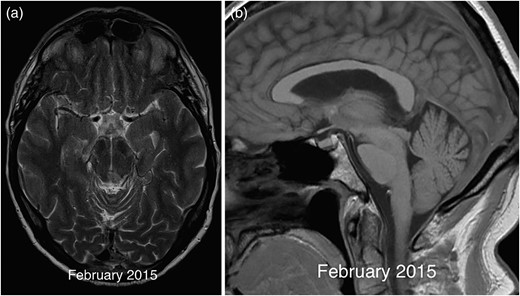

Following a transient deterioration in balance following the biopsy, the patient clinically improved with subtotal resolution of his oculomotor symptoms. This was mirrored by a mild improvement in the degree of brainstem sagging on a follow-up MRI from 2015, further supporting a diagnosis of SIH (Fig. 4). The patient declined a lumbar puncture and spinal imaging to assess for signs of a CSF leak.

Axial T2 image in 2015 (a) demonstrating resolution of the midbrain mass except for a small biopsy scar. The corresponding sagittal T1 (b) image shows a mild improvement in the degree of brainstem sagging with less marked flattening of the pons compared with previous imaging.